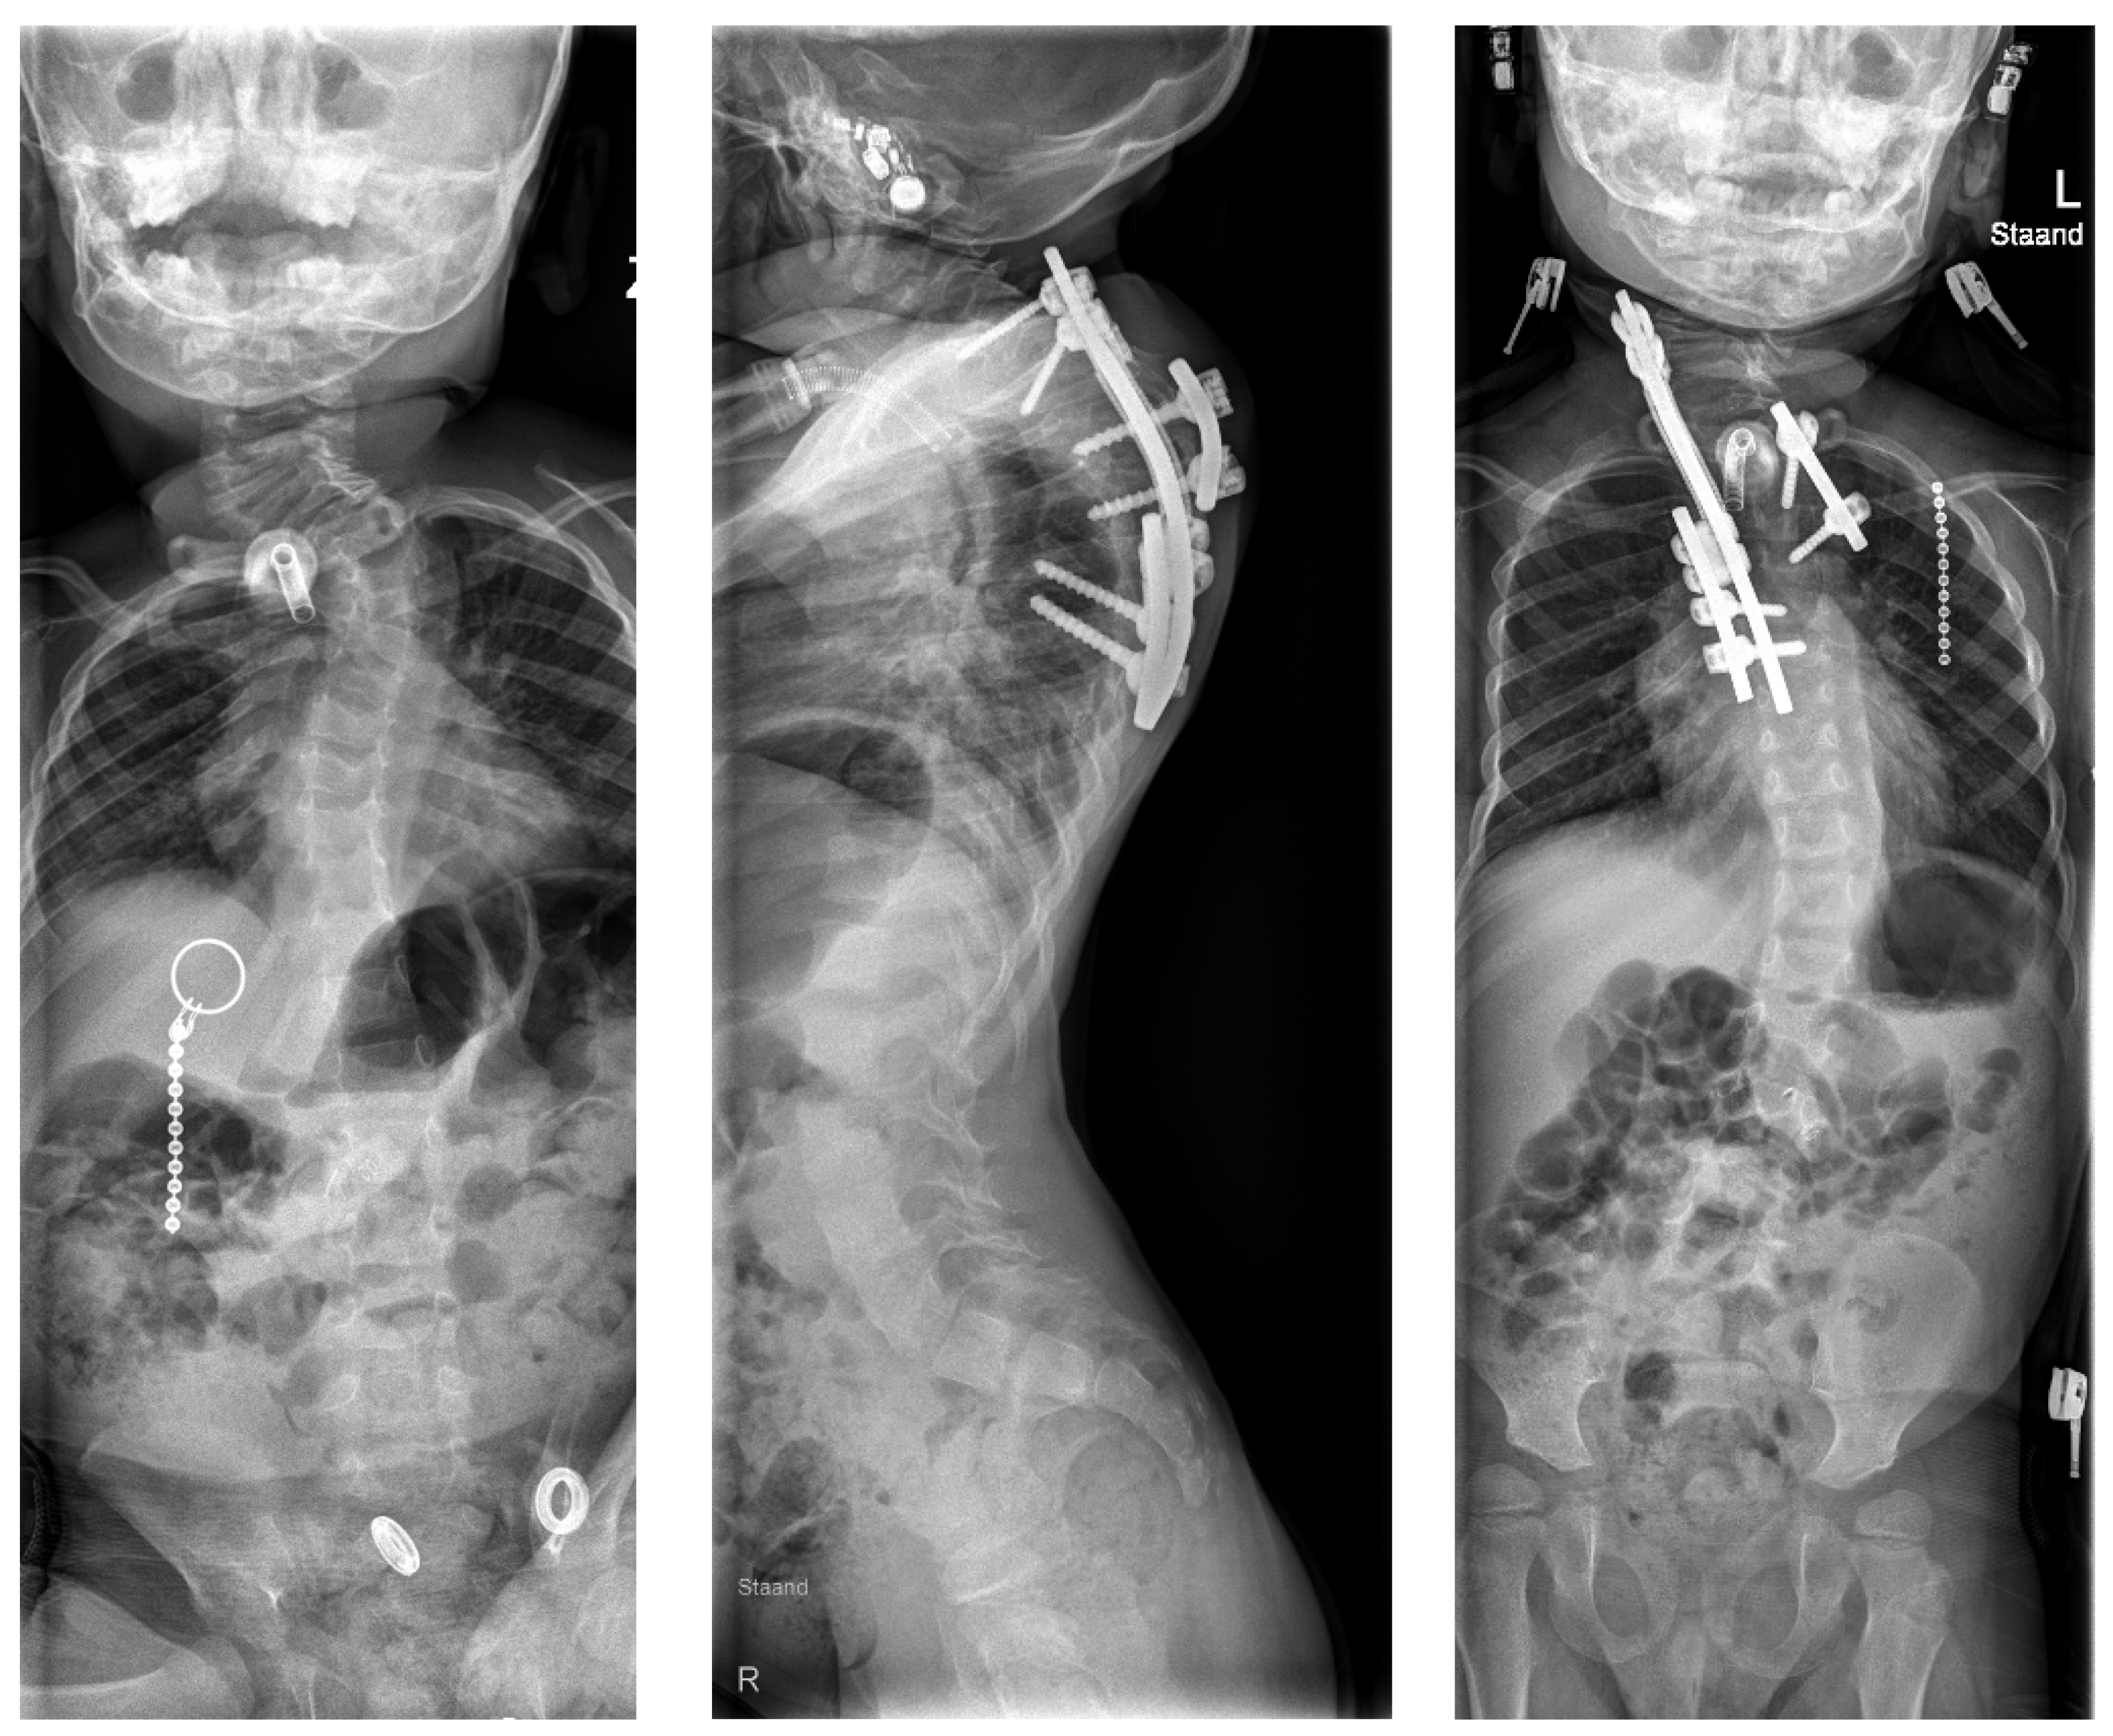

6.3. Clinical Experience with Spinal Prosthesis